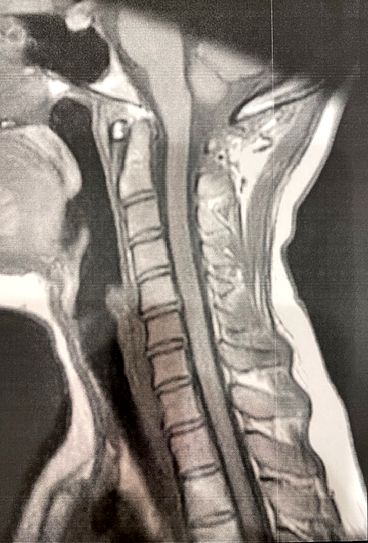

MRI検査では特に脳に異常は認められませんでした。

但し、首には重度のストレートネックが確認されました。

※印刷した画像を写真で撮りましたので、画質は良くないです。

ストレートネック自体は、現代では珍しい事ではありません。スマートフォンの利用で、前屈みの体制を取る方が多いからです。ただ、皆がなるものだから仕方ないとは言い切れない部分があります。ここでもう一度先ほどの方の首を見てみましょう。

完全に首がストレートになっています。一般的にストレートネックを紹介する画像では、わかりやすい解説するためにストレートネックの症例は首が真っ直ぐになっていますが、実際にはそこまで極端な方は限られています。カーブの曲がりが減り真っ直ぐに近い状態になっているが典型例です。この方のレベルまでに真っ直ぐになってしまうと、ほぼ頭痛か首の痛みで困っている方です。